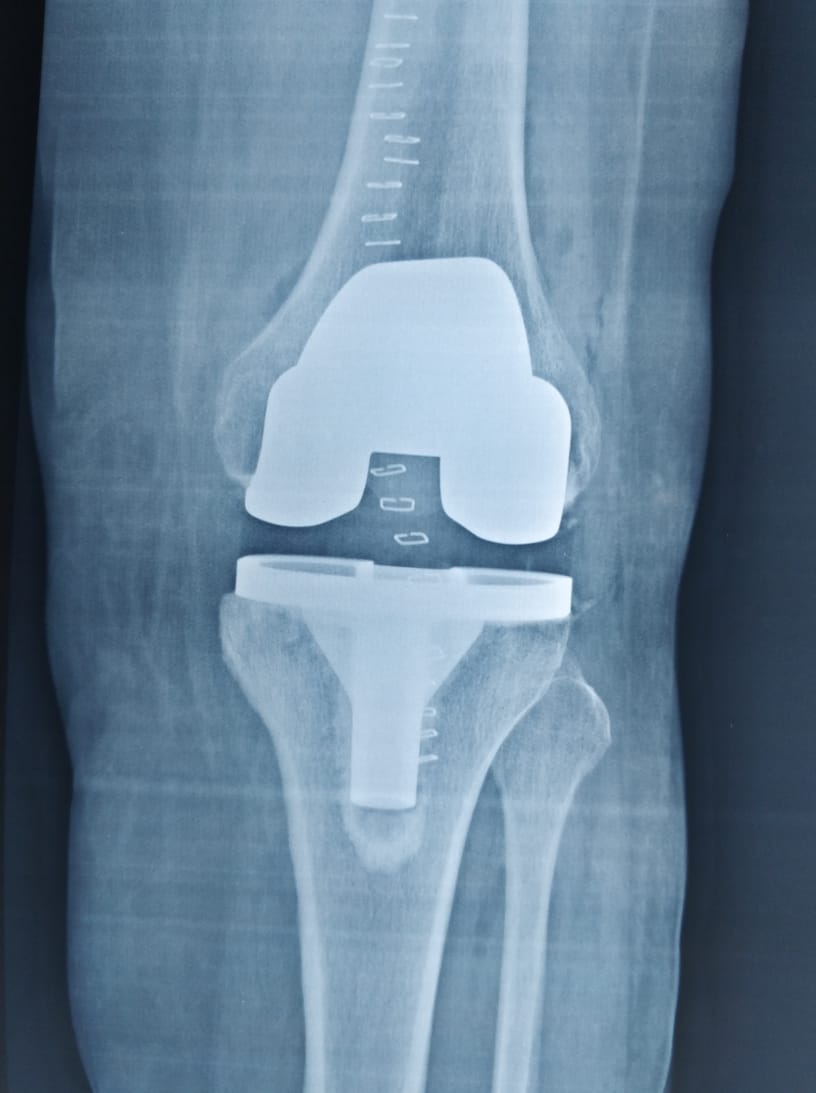

Dr. Nilesh Hirekhan Orthopedic specializes in orthopedic surgery with a focus on joint replacement, sports medicine, and trauma surgery.

Dr. Nilesh Hirekhan treats a wide range of orthopedic conditions including arthritis, fractures, ligament injuries, tendonitis, and joint disorders.